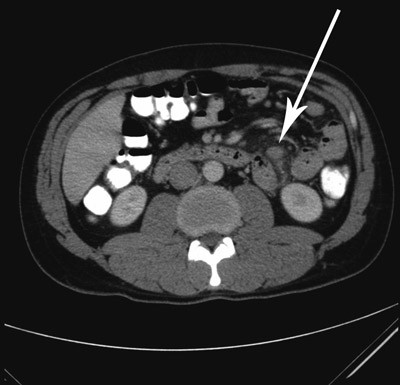

CT abdomen viste kun reaktive forandringer i fettvev mesenterialt samt multiple og forstørrede lymfeknuter i dette området (fig 1). Blodprøvene viste SR 35 mm (2 – 10 mm), CRP 145 mg/l, hemoglobin 13,6 g/100 ml (13,4 – 17,0 g/100 ml), leukocytter 7,7 · 10 9/l (3,5 – 10 · 10⁹/l), ASAT 125 U/l (15 – 45 U/l), ALAT 136 U/l (10 – 70 U/l), GT 79 U/l (10 – 80 U/l), ALP 96 U/l (35 – 105 U/l). På grunnlag av kliniske funn og blodprøver ble det startet med antibiotika i form av piperacillin-tazobactam.